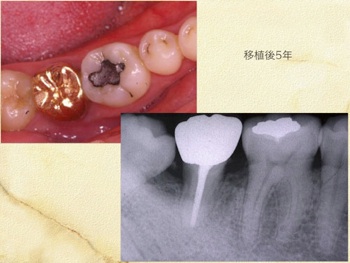

当クリニックでは自家歯牙移植を用いて、失われた歯牙を補う治療を行なっております。

自家歯牙移植の歴史は古く、近年の研究で歯牙、歯根膜へ配慮し施術することでその成績は格段に上がっております。

当クリニックでは約14年前より行なっており、約90%の成功率です。(尚10%の中には途中未来院になり判別不可能となった方も含まれますことをご理解ください。)

適応となる方は様々な条件により限られますが、適切に行なえば皆様に大きなメリットを提供できる治療方法です。